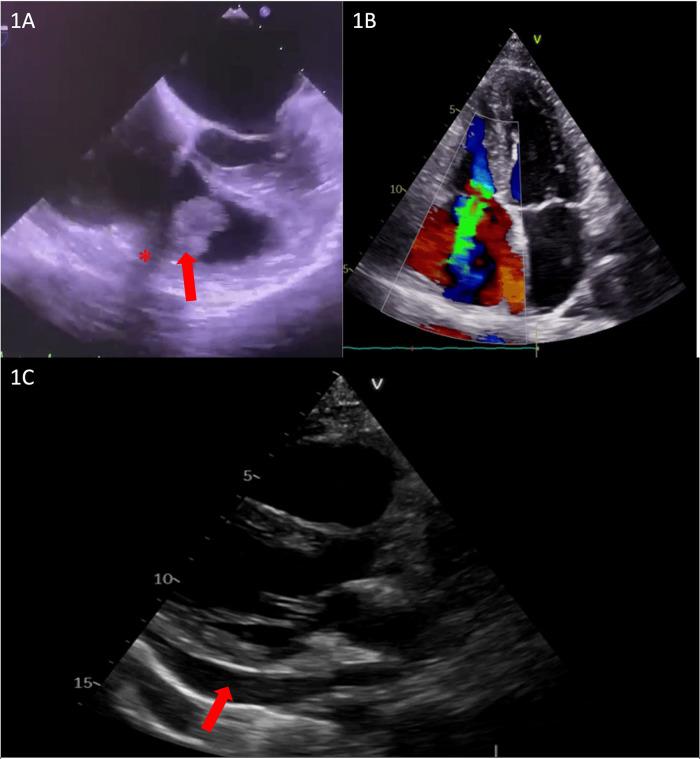

We report the case of a 39-year-old pregnant woman with a history of drug abuse who was admitted to the cardiology department with a diagnosis of tricuspid valve endocarditis. After the multidisciplinary team decided on a conservative treatment with antibiotherapy, the pregnancy was closely monitored. After 4 weeks of treatment, the patient developed extreme thoracic pain and pericardial effusion that was considered infectious and did not require urgent surgery. One month after giving birth to her baby, the patient was admitted to our hospital for the completion of the preoperative protocol. During this admission, multimodal imaging revealed a penetrating metallic foreign body in the wall of the right ventricle. The patient was finally admitted to the Cardiovascular Surgery Unit, where she underwent surgical removal of the foreign body and a complex tricuspid valve repair. The postoperative course was uneventful, and our patient was discharged from the ICU 2 days later.

我们报告了一例39岁有药物滥用史的孕妇,她因诊断为三尖瓣心内膜炎而入住心内科。在多学科团队决定采用抗生素进行保守治疗后,对该孕妇进行了密切监测。治疗4周后,患者出现极度胸痛和心包积液,考虑为感染性,无需紧急手术。在生下婴儿一个月后,患者因完成术前方案而入住我院。在此期间,多模态成像显示右心室壁有一个穿透性金属异物。患者最终入住心血管外科病房,在那里接受了异物手术取出及复杂的三尖瓣修复。术后过程顺利,患者于2天后从重症监护病房出院。